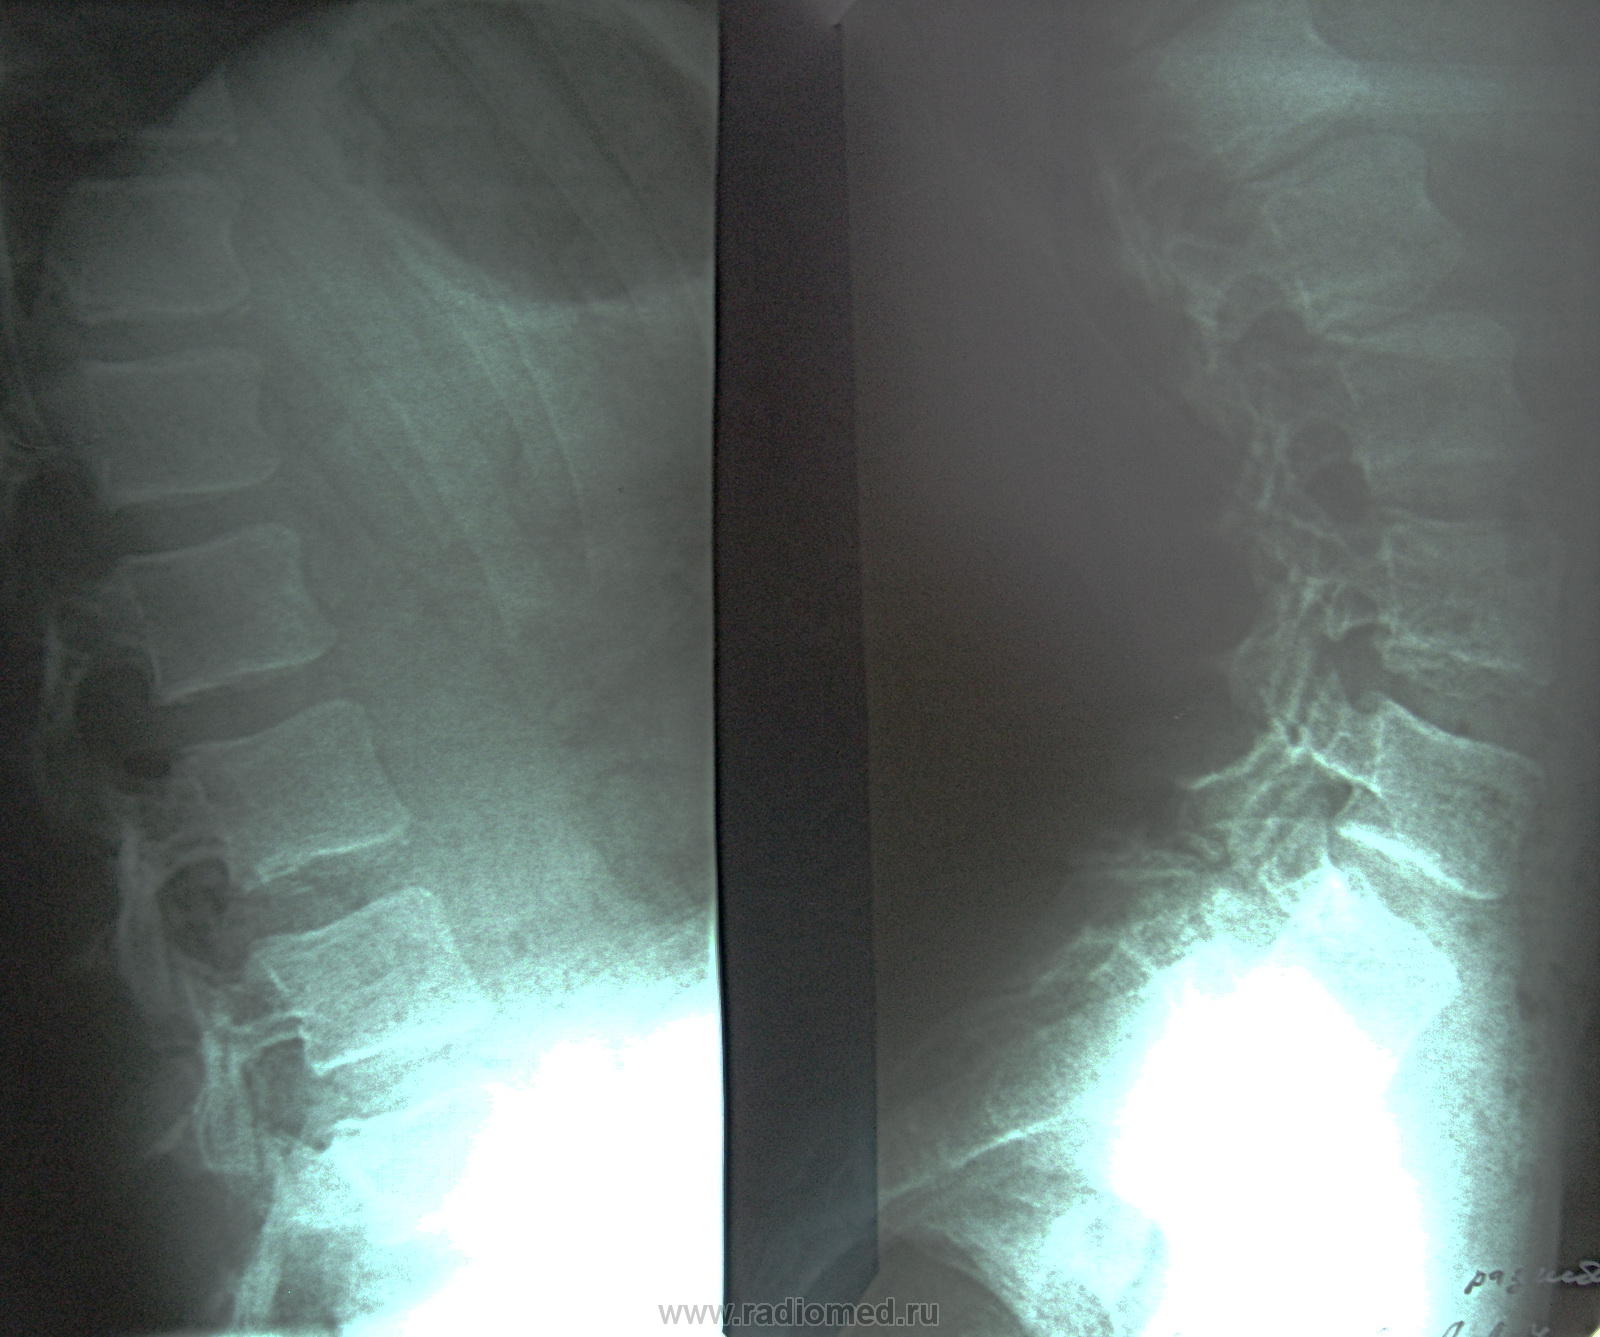

Пол пациента: Женский пол Тип патологии: Травма Область исследования: Скелетно-мышечная система Методы исследования: Rg после тренировки почувствовала жалобы на резкие боли в области крестца. Прошу прощения коллег за качество снимков. У меня возникло подозрение о листезе? https://radiomed.ru/sites/default/files/styles/case_slider_image/public/user/712/sl273623.jpg?itok=1nQbEQ2A ID:13720 Wed, 27/04/2011 - 19:55 #1 Nela Offline Last seen: 6 years 2 months ago Joined: 12.05.2009 - 20:43 Posts: 1847 Листез есть, на мой взгляд. А нельзя без вспышки сфотографировать? Wed, 27/04/2011 - 20:47 #2 Шаба Offline Last seen: 3 years 5 months ago Joined: 19.08.2010 - 22:01 Posts: 122 за листез Wed, 27/04/2011 - 20:49 #3 Глазков Игорь А... Offline Last seen: 10 months 2 weeks ago Joined: 19.12.2008 - 20:41 Posts: 1597 вспышки, но что-то не выходит лучше. Прийди к Себе Wed, 27/04/2011 - 21:07 #4 Ola-la Offline Last seen: 11 months 1 week ago Joined: 06.12.2008 - 09:33 Posts: 1786 Похоже да, истинный спондилолистез. https://www.instagram.com/pediatricradiology/ Wed, 27/04/2011 - 22:55 #5 Rg-Doc Offline Last seen: 8 years 10 months ago Joined: 22.03.2008 - 12:25 Posts: 333 Ola-la wrote: Похоже да, истинный спондилолистез. А где похоже, что истинный? Thu, 28/04/2011 - 07:33 #6 Rex Offline Last seen: 14 years 8 months ago Joined: 26.04.2011 - 21:03 Posts: 35 ЗдесьПриложения: Даже когда уверен на 100%, непременно подвернется исключение из правил... Thu, 28/04/2011 - 08:48 #7 Rg-Doc Offline Last seen: 8 years 10 months ago Joined: 22.03.2008 - 12:25 Posts: 333 Игорь Артурович, не могли бы Вы еще раз сфотографировать снимки с более лучшим качеством? Thu, 28/04/2011 - 18:40 #8 Глазков Игорь А... Offline Last seen: 10 months 2 weeks ago Joined: 19.12.2008 - 20:41 Posts: 1597 придёт. что должно случиться. то обязательно переснему. Прийди к Себе Thu, 28/04/2011 - 21:20 #9 Игорь Иванович Offline Last seen: 3 years 10 months ago Joined: 23.01.2010 - 14:56 Posts: 3695 Только этот спондилолистез не нужно связывать с тренировкой.

Листез есть, на мой взгляд. А нельзя без вспышки сфотографировать?

Похоже да, истинный спондилолистез.

А где похоже, что истинный?

Только этот спондилолистез не нужно связывать с тренировкой.